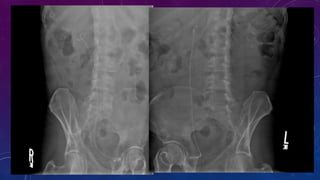

• Multiple pelvic phleboliths.

• Small well-defined round osseous lesions in the left

side of the abdomen, adjacent to midline represent

calcified lymph node in the para-aortic and left

common iliac groups, also visualized on the

corresponding CT.